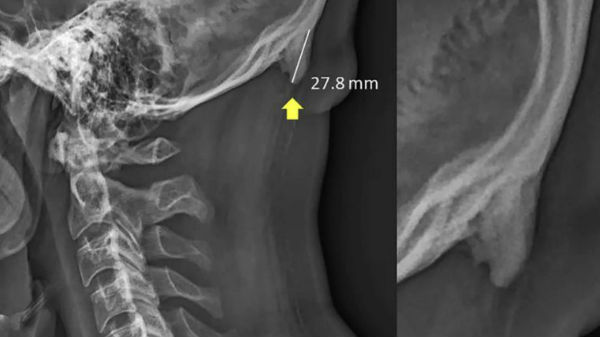

ಇತ್ತೀಚೆಗೆ ಆಸ್ಟ್ರೇಲಿಯಾದ ಕ್ವೀನ್ಲ್ಯಾಂಡ್ನ ಸನ್ಶೈನ್ ಕೋಸ್ಟ್ ವಿಶ್ವವಿದ್ಯಾಲಯದ ಸಂಶೋಧಕರು ಈ ಬಗ್ಗೆ ಅಧ್ಯಯನ ನಡೆಸಿದಾಗ ಇಂತಹದೊಂದು ವಿಷಯ ಬೆಳಕಿಗೆ ಬಂದಿದ್ದು, ಯುವಕರು ತಮ್ಮ ತಲೆಬುರುಡೆಯ ಹಿಂಭಾಗದಲ್ಲಿ ಕೊಂಬಿನಂತಹ ಹೊಸ ಅಂಗ ಬೆಳೆಯುತ್ತಿದೆ ಎಂದು ತಿಳಿಸಿದ್ದಾರೆ. ಅಧ್ಯಯನ ಹೇಳುವ ಪ್ರಕಾರ, ಸ್ಮಾರ್ಟ್ಫೋನ್ಗಳು ಮತ್ತು ಇತರ ಹ್ಯಾಂಡ್ಹೆಲ್ಡ್ ಸಾಧನಗಳು ಮಾನವ ರೂಪವನ್ನು ನಿಯಂತ್ರಿಸುತ್ತಿವೆ. ಇದು ಇತ್ತೀಚಿಗೆ ಹೆಚ್ಚು ಕಂಡುಬಂದಿದೆ ಎಂದು ಸಂಶೋಧಕರು ತಿಳಿಸಿದ್ದಾರೆ.

ಕಳೆದ ವರ್ಷ ಈ ಬಗ್ಗೆ ಸಂಶೋಧನೆ ನಡೆಸಲಾಗಿದ್ದು, 18-86 ವರ್ಷದ 1,200 ಜನರನ್ನು ಅಧ್ಯಯನಕ್ಕೆ ಒಳಪಡಿಸಲಾಗಿದೆ. ಇವರಲ್ಲಿ ಶೇ. 33 ಜನರಿಗೆ ಅಸ್ಥಿಪಂಜರದ ರೂಪಾಂತರವಾಗಿ ತಲೆಯ ಹಿಂಭಾಗದಲ್ಲಿ ಕೋಡು ಬೆಳೆದಿರುವ ವಿಚಾರ ತಿಳಿದುಬಂದಿದೆ. ಈ ಕೋಡು ಬೆಳೆಯಲು ಮೊಬೈಲ್ ಬಳಕೆ ಅಧಿಕವಾಗಿದ್ದೆ ಕಾರಣ ಎನ್ನಲಾಗಿದ್ದು, ಚಿಕ್ಕ ವಯಸ್ಸಿನಿಂದಲೂ ಮೊಬೈಲ್ ಬಳಕೆ ಮಾಡುತ್ತಿದ್ದರೆ ಈ ಬದಲಾವಣೆ ಕಂಡುಬರುವ ಸಾಧ್ಯತೆ ಹೆಚ್ಚು ಎಂದು ಅಧ್ಯಯನಕಾರರು ತಿಳಿಸಿದ್ದಾರೆ.

ಇಂದಿನ ಯುವಜನತೆ ಮೊಬೈಲ್ ಸೇರಿದಂತೆ ಗ್ಯಾಜೆಟ್ಗಳನ್ನು ಸದಾ ಹಿಡಿದಿರುತ್ತಾರೆ. ಮೊಬೈಲ್ ನೋಡಲು ಕತ್ತನ್ನು ಕೆಳಮುಖ ಮಾಡಿಕೊಳ್ಳಬೇಕು. ಇದರಿಂದ ಬೆನ್ನು ಮೂಳೆಯ ಬದಲಾಗಿ ತಲೆ ಹಿಂಭಾಗದಲ್ಲಿರುವ ಸ್ನಾಯುವಿಗೆ ಭಾರ ವರ್ಗಾವಣೆ ಆಗುತ್ತದೆ. ಹಾಗಾಗಿ, ಮಾನವನ ತಲೆಬುರುಡೆಯಿಂದ ಕುತ್ತಿಗೆಯ ನಡುವೆ ನಿಧಾನವಾಗಿ ಮೂಳೆ ಆಕಾರದ ಅಂಗ ಬೆಳೆದುಕೊಳ್ಳುತ್ತದೆ ಎಂದು ಅಧ್ಯಯನ ಹೇಳಿದೆ. ಈ ಕೋಡು ಸುಮಾರು 3-5 ಮಿಲಿಮೀಟರ್ವರೆಗೆ ಬೆಳೆಯಲಿದೆ ಎಂದು ತಿಳಿಸಿದೆ.

ಮೊಬೈಲ್ ಅಥವಾ ಇತರೆ ಹ್ಯಾಂಡೆಲ್ಡ್ ಪರದೆಗಳಲ್ಲಿ ಏನಾಗುತ್ತಿದೆ ಎಂಬುದನ್ನು ಅರ್ಥಮಾಡಿಕೊಳ್ಳಲು ತಮ್ಮ ತಲೆಯನ್ನು ಮುಂದಕ್ಕೆ ಬಾಗಿಸಬೇಕಾಗುತ್ತದೆ. ಇದರಿಂದ ಕಿರಿಯ ವಯಸ್ಕರಲ್ಲಿ ಮೂಳೆ ಬೆಳವಣಿಗೆಯು ಬದಲಾಗುತ್ತಿದೆ. ಆಧುನಿಕ ತಂತ್ರಜ್ಞಾನದ ಬಳಕೆಯು ದೇಹದ ಭಂಗಿಯನ್ನು ಬದಲಿಸುವಂತೆ ಸೂಚಿಸುತ್ತದೆ. ಈ ಕೋಡು ಒಂದು ದಿನ ಅಥವಾ ಒಂದು ವರ್ಷದಲ್ಲಿ ಬೆಳೆಯುವಂಥದ್ದಲ್ಲ. ಇದಕ್ಕೆ ಅನೇಕ ವರ್ಷಗಳೇ ಹಿಡಿಯುತ್ತವೆ ಎಂದು ಅಧ್ಯಯನಕಾರರು. ತಿಳಿಸಿದ್ದಾರೆ.